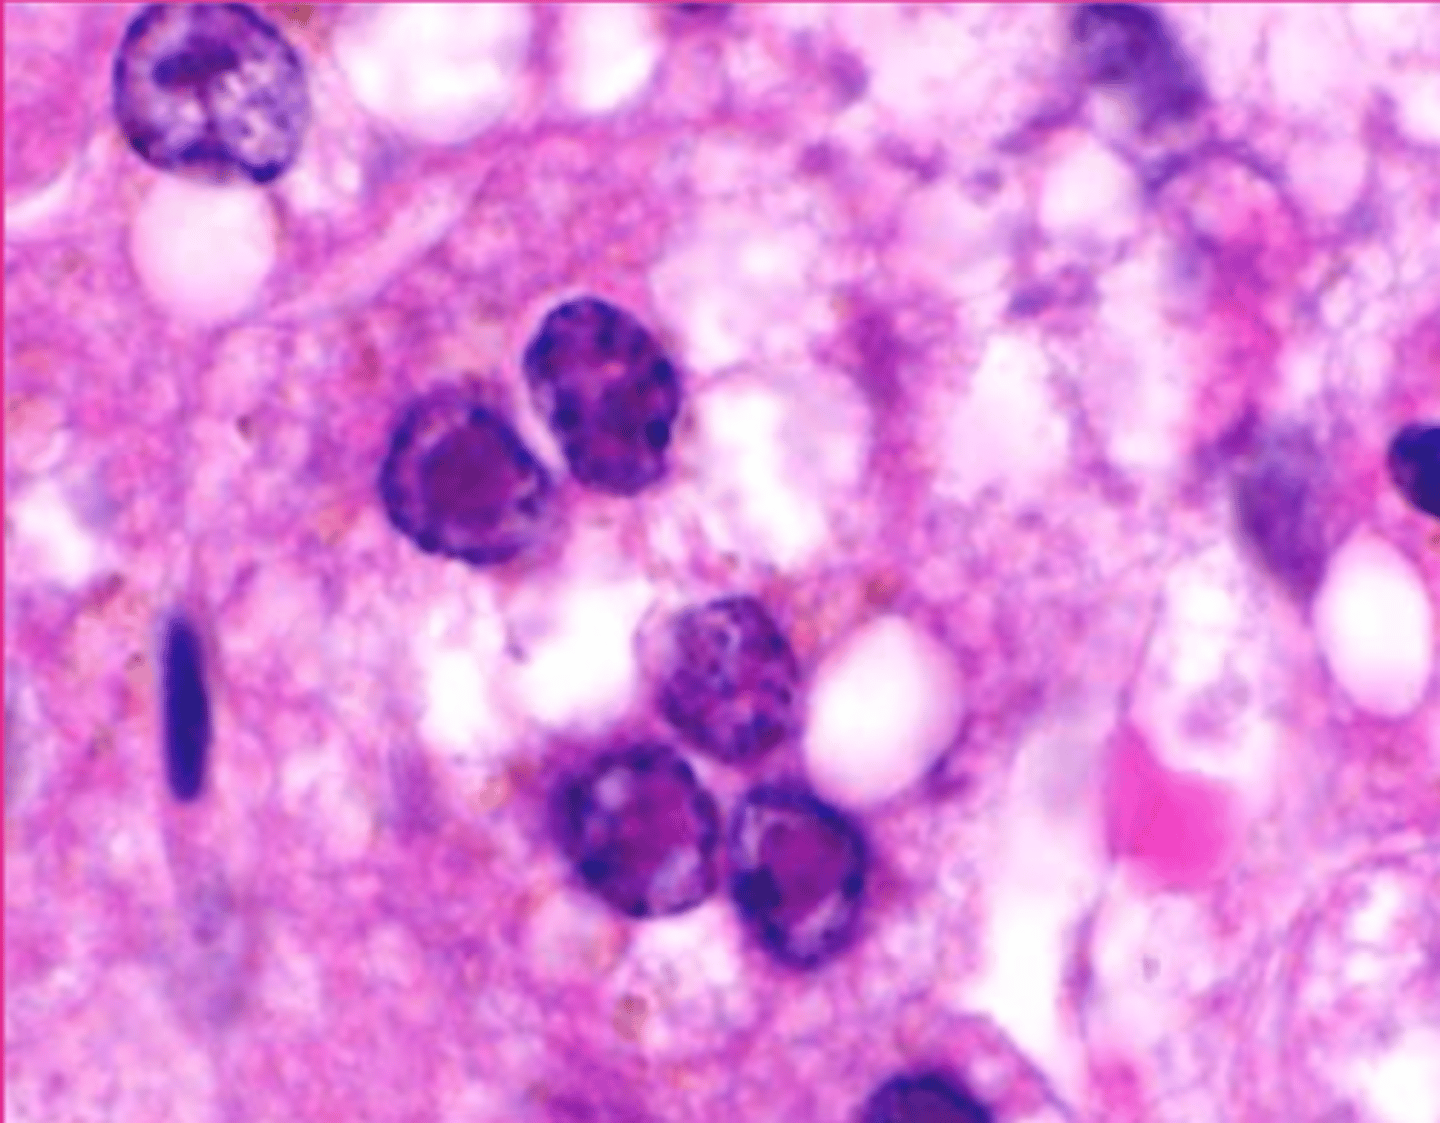

Russel bodies in Mott cells

These are plasma cells. what is circled?